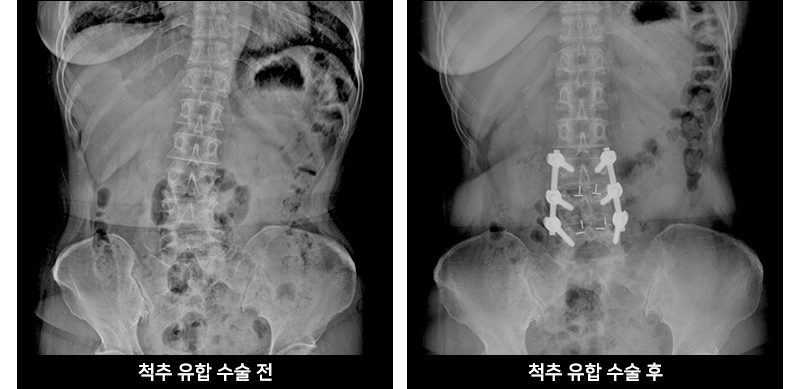

척추유합술이란?

척추유합술은 척추 뼈 사이에 뼈를 이식하여 두 개의 뼈를 하나로 합치는 수술법으로,

척추전방전위증이나 고도의 협착증 같은 경우 시행하는 치료법입니다.

정상 근육 및 뼈를 광범위하게 제거했던 기존의 방식과는 달리, 교정할 부분만을

첨단 내시경 장비 및 미세현미경 장비로 정확하게 관찰하고 교정함으로써

척추간의 유합률을 높이고 치료 후 회복과정을 더욱 줄였습니다.